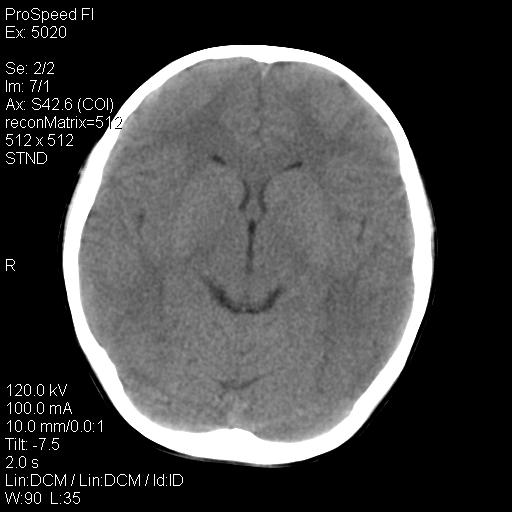

标题: PED1637:M 6Y 顶部无痛性包块两月。 [打印本页]

标题: PED1637:M 6Y 顶部无痛性包块两月。

2、颅骨局部缺失,边缘光滑、整齐

颅骨的病损表现为内外颅骨板层不规则的锋利的破坏,形成“斜边缘”,有一定的特点

颅骨为好发部位,生长缓慢,常位于顶骨、枕骨及颞骨,表现为颅骨缺损,呈圆形或椭圆形,边界清,无硬化

事发冠状缝与矢状缝交界区,密度较低,考虑表皮样囊肿可能性大,其次不除外嗜酸性肉芽肿